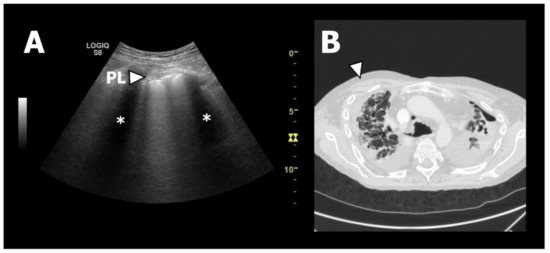

3.2. LUS Findings

4.1. LUS Findings